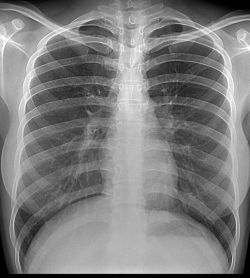

Digital X-Ray

What is Digital X-Ray?

X-Ray Chest even today is the most commonly investigation done world-wide. While other types of modalities are more frequently used today, X-Rays are still required for

Digital X-Rays are digital images that are clearer, and allow for better detection of diseases.